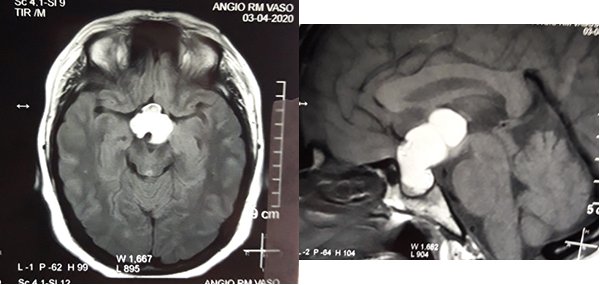

En RM de cerebro se observa lesión espacio ocupante selar-supraselar con aspecto multilobulado que invade cisterna interpeduncular y desplaza estructuras del tercer ventrículo. La misma es hiperintensa espontáneamente en T1 con captación heterogénea de contraste, hiperintensa en T2 (Figura 1). En secuencia de angioresonancia se observa su relación medial respecto a arterias carótidas no comprometiendo las mismas (Figura 2). A partir de éstas imágenes obtenidas en resonador 3 Tesla, en el Departamento de Innovación Tecnológica del Instituto Cardiológico de la Ciudad de Corrientes se realizó un proceso de segmentación de las distintas partes de interés (tumor, arterias, nervios ópticos y globos oculares). Para esto se utilizó el software “Open Source 3D Slicer (versión 4.11)” (Figura 3). Una vez segmentadas las regiones de interés, se realizó, mediante una impresora 3D “MAX” de la empresa Creatbot, un modelo 3D cuyos materiales consistieron en poliácido láctico (PLA) y poliuretano termoplástico (Figuras 4 y 5). Con el mismo, se realizó la planificación del abordaje quirúrgico.

Figura 1: RM en secuencia T1 cortes a) 1axial, se observa lesión espontáneamente hiperintensa y su relación con vasos del polígono de Willis. b) RM en secuencia T1 corte sagital, donde se observa extensión supraselar de la lesión comprimiendo lamina terminalis

Figura 2: RM en secuencia de angioresonancia a) proyección coronal posterior, observándose arterias cerebrales posteriores circunscribiendo la lesión b) proyección oblicua izquierda y su relación con arterias carótidas y ramas de bifurcación.